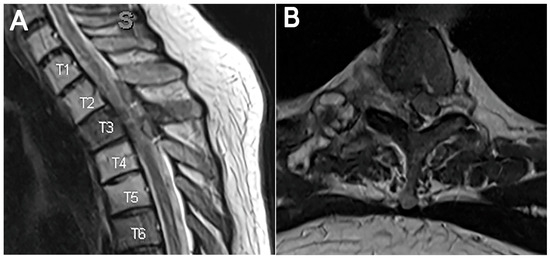

Using Endoscopic Approaches in the Surgical Management of Spinal Metastatic Disease

Patients with spinal metastasis often benefit from surgical intervention for debulking to improve neurologic deficits, reduce spinal cord or root compression, and ameliorate pain. Traditionally, large, open fusions have been used to achieve adequate decompression of neural structures. These types of interventions are frequently associated with significant blood loss, prolonged hospitalizations, and increased risk of surgery-related complications, which can delay postoperative chemotherapy and radiation therapies. Endoscopic spine approaches allow access to the spinal cord and nerve roots with minimal soft tissue disruption, which has been shown to reduce risks associated with open surgery in other contexts. Furthermore, the smaller incision, reduced blood loss, ability to position incisions away from radiation fields, and lower risk profile in high-risk patients may provide an effective solution to spinal metastases in appropriately selected cases. Here, we present two cases of spinal metastases successfully managed with spinal endoscopy and recommend the consideration of this approach for similar scenarios. Full article